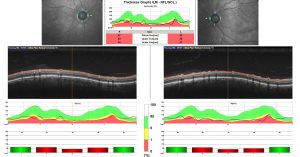

La tomografia a coerenza ottica (OCT) è un test di imaging non invasivo che utilizza le onde di luce per scattare foto della retina, e in particolare della macula. La macula è una parte della retina deputata alla visione a colori e ad alta definizione.

Con l’OCT possono essere analizzati e mappati tutti gli strati retinici, inoltre è possibile rilevare lo spessore retinico. Questi dati aiutano a effettuare una corretta diagnosi e a fornire delle indicazioni per il trattamento del glaucoma e delle patologie retiniche, malattie come la degenerazione maculare senile e la retinopatia diabetica.